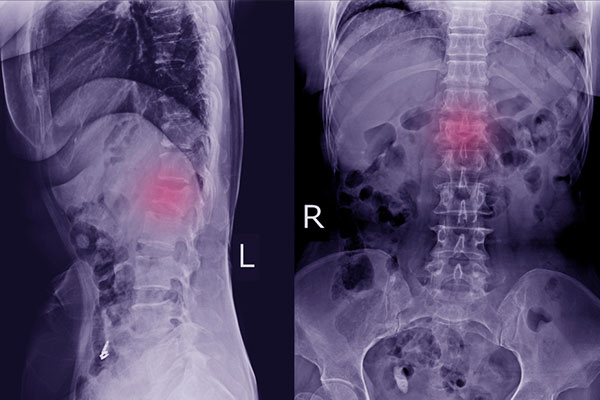

2. Chẩn đoán hình ảnh X-quang, CT scan, MRI

Công nghệ hình ảnh không chỉ được áp dụng trong việc chẩn đoán bệnh xương khớp mà còn được ứng dụng rộng rãi trong quá trình thăm khám và điều trị nhiều bệnh lý khác. Thông qua hình ảnh chụp lại chi tiết cấu trúc và hình dạng bên trong khớp, bác sĩ có thể dễ dàng nhìn ra tổn thương mà xương khớp đang gặp phải và đâu là lý do khiến xương khớp của bạn bị đau nhức, sưng tấy.